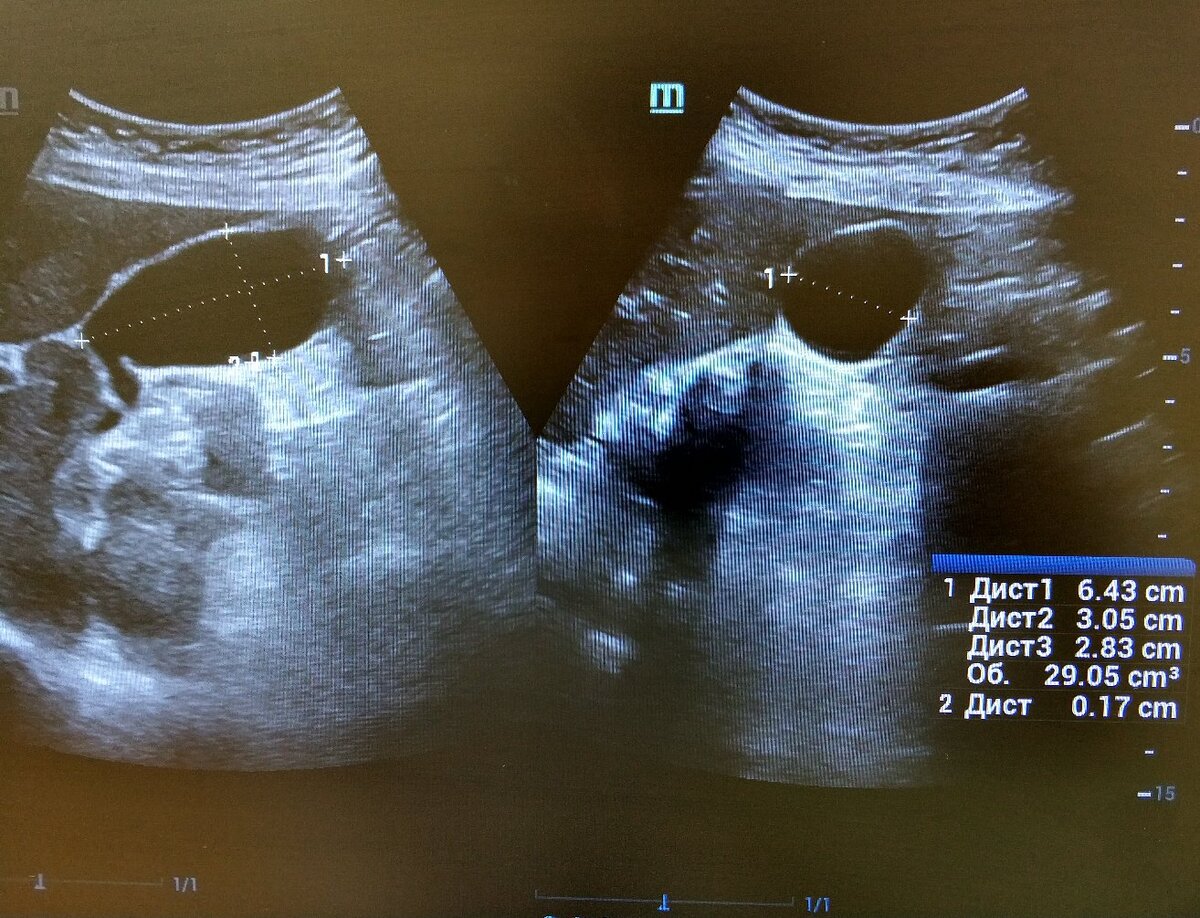

✅Реальность: Цель исследования это фракция опорожнения, клиническое значение при снижении менее 40%, то есть пузырь не сокращается. Считается по объему пузыря на ультразвуке либо методом сцинтиграфии.

✅Реальность: для получения коэффициента опорожнения достаточно одного измерения через 20 минут, максимальное сокращение через 30 минут в сомнительных случаях.